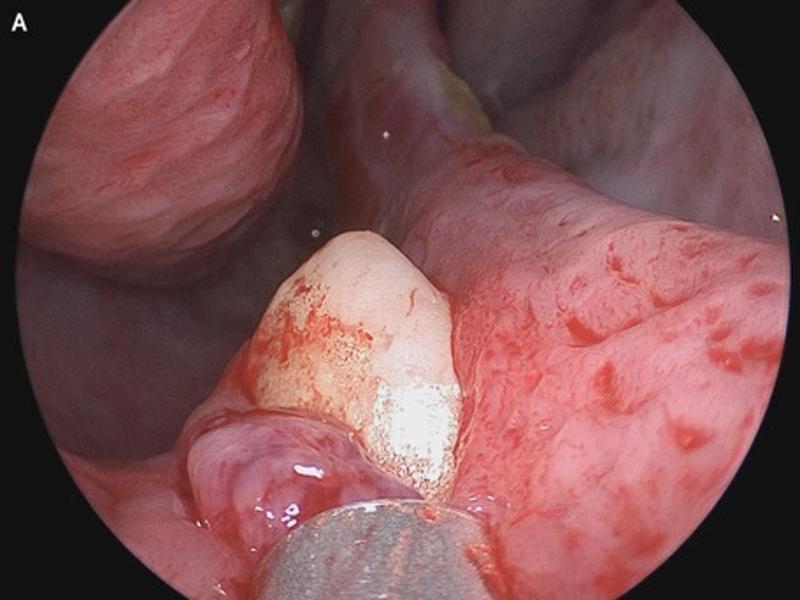

Adamın burnunun içinde büyüyen ve nefes alma güçlüğüne neden olan ektopik diş burada görülüyor (The New England Journal of Medicine)

Bir burun muayenesi yöntemi olan rinoskopiyle sağ burun deliğinin tabanında "sert, hassas olmayan, beyaz bir kitle" olduğu belirlendi.

Paranazal sinüslerin veya burun boşluğunu çevreleyen hava dolu yerlerin bilgisayarlı tomografi (BT) taraması sağ burun boşluğunda "ters dönmüş ektopik dişle uyumlu, net hatlara sahip radyodens bir kitle" olduğunu gösterdi.

Hastanın 14 mm uzunluğundaki dişi ameliyatla alındı. Doktorlar ameliyattan üç ay sonra yapılan kontrolde hastanın nefes darlığının düzeldiğine dikkat çekti.